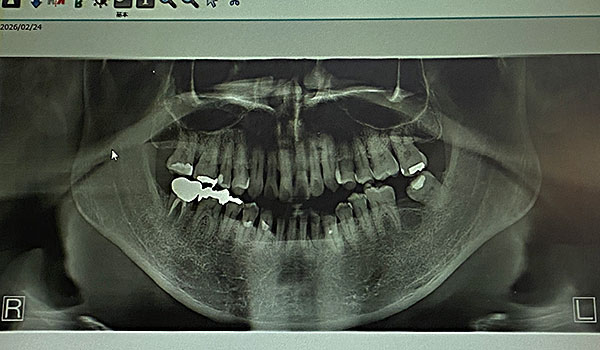

夕刻田崎と儂が歯医者。

帰路田崎オカダヤ菅又首腰牽引。

菅又はかかりつけ歯医者で詰め物直す。